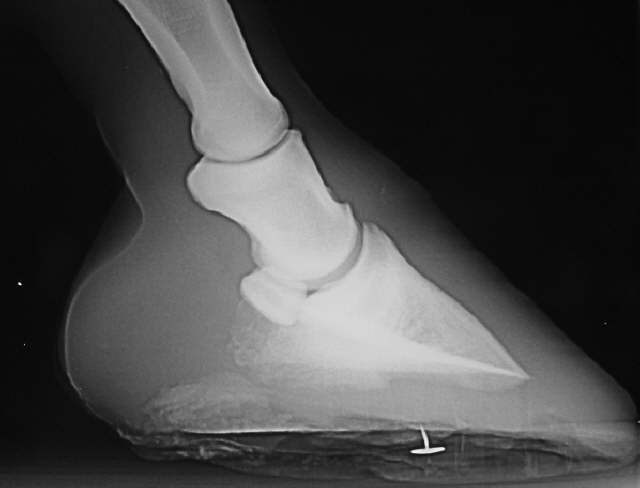

Flacher Huf

Flacher Huf mit gequetschten Trachten und Atrophie der Hufbeinäste. Der Reissnagel dient als Orientierung für den Schmied.